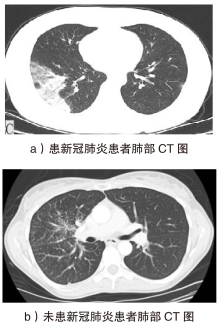

随着智能医疗系统的快速发展,标注数据的匮乏已成为制约研究进展的关键因素之一,知识蒸馏作为一种有效的数据利用策略能够缓解这一问题。然而,在智能医疗领域,模型通常用于替代人工进行影像、数据的诊断,这不仅对医疗信息隐私保护提出了更高要求,还强调了模型精度对诊断结果准确性的决定性影响。因此,文章提出一种结合差分隐私的知识蒸馏方案,并将其应用于图神经网络模型,在知识蒸馏过程中保护用户敏感信息的同时,确保较高的医疗诊断准确率。为验证所提方法的有效性,文章构建了图注意力网络(GAT)模型和卷积神经网络(CNN)模型作为对照组,并采用3种实际医疗图像数据集进行实验。结果表明,文章所提方法在GAT模型的准确率较在CNN模型的准确率有所提升,对应在3个数据集上分别由61%提升至68%、83%提升至93%、67%提升至80%。鉴于GAT模型的高资源开销,文章进一步设计了一种轻量化GAT模型架构。该轻量化模型在显著降低资源消耗的同时,仍保持优于CNN模型的分类性能,从而在差分隐私保护的前提下,有效提升医疗诊断效果。